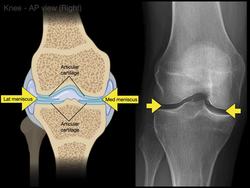

The Noted Anatomist

Anatomy of Knee X-rays

Higher Ed

This video tutorial presents the anatomy of knee x-rays: 0:00. Intro to knee x-rays 0:14. Standard knee series for x-rays 0:21. AP view (right knee) 4:21. Lateral view (right knee) 5:56. Sunrise view (right knee) 7:19. In-a-Nutshell...